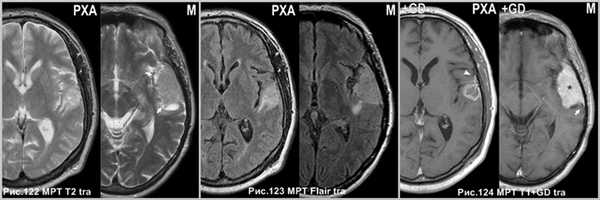

В отличии от ПКА - менингиома чаще солидная опухоль, и лишь в редких случаях содержит кисты; контрастируется гомогенно, так же имеет “дуральный хвост”, редко сопровождается перифокальным отеком.

Менингиома чаще не сопровождается отёком (стрелка на рис.122) и гомогенно накапливает контрастный агент (звёздочка на рис.124), а так же имеет “дуральные хвосты” (стрелки на рис.124), подобно ПКА (головка стрелки на рис.124). Менингиома и ПКА в режиме Flair (рис.123).